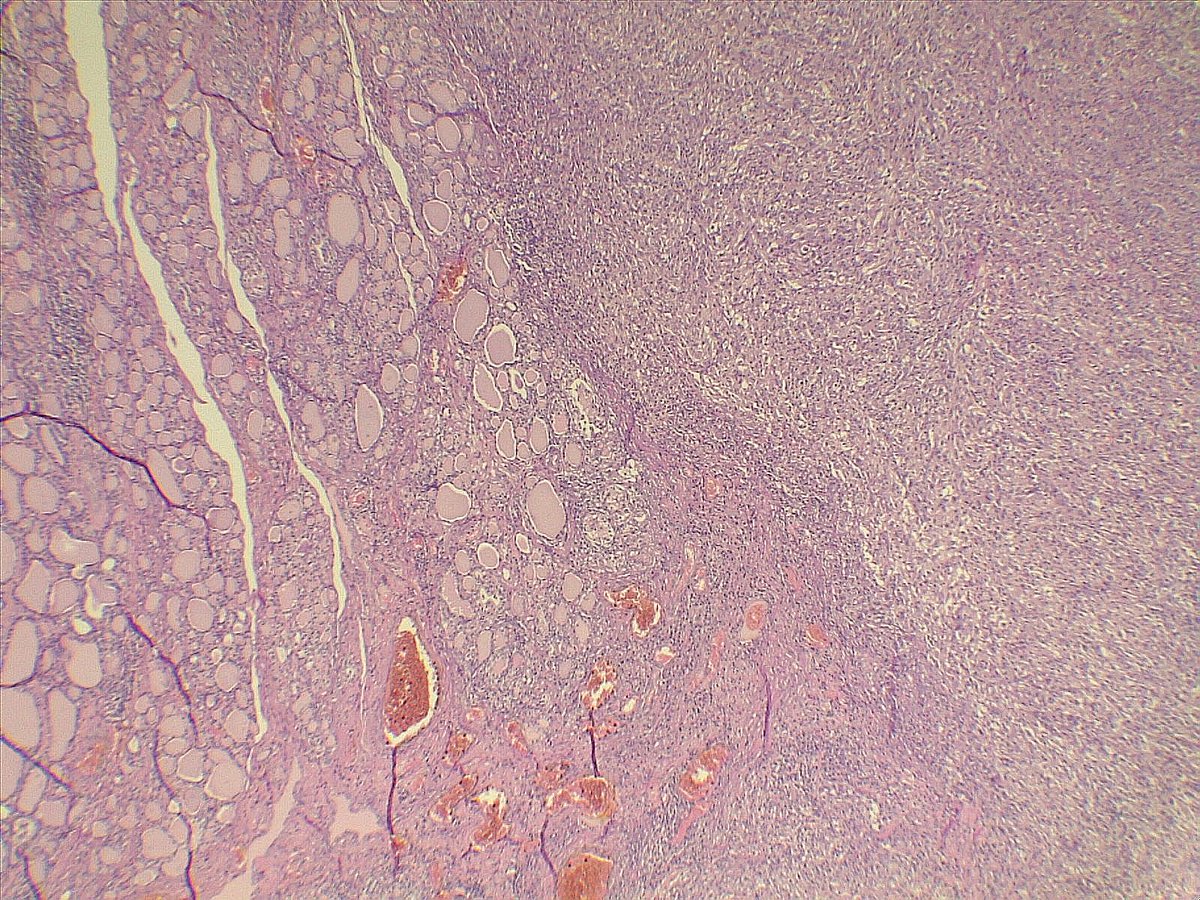

Middle-aged patient with a mass in a cervical vertebra. There is a hx of sarcoma. This was not my own case, but I was fortunate enough to see it and learn from it, hence the reason I'm sharing. Morphology is 🔑 #IHCPath provided is PCK. What's your diagnosis? #PathTwitter